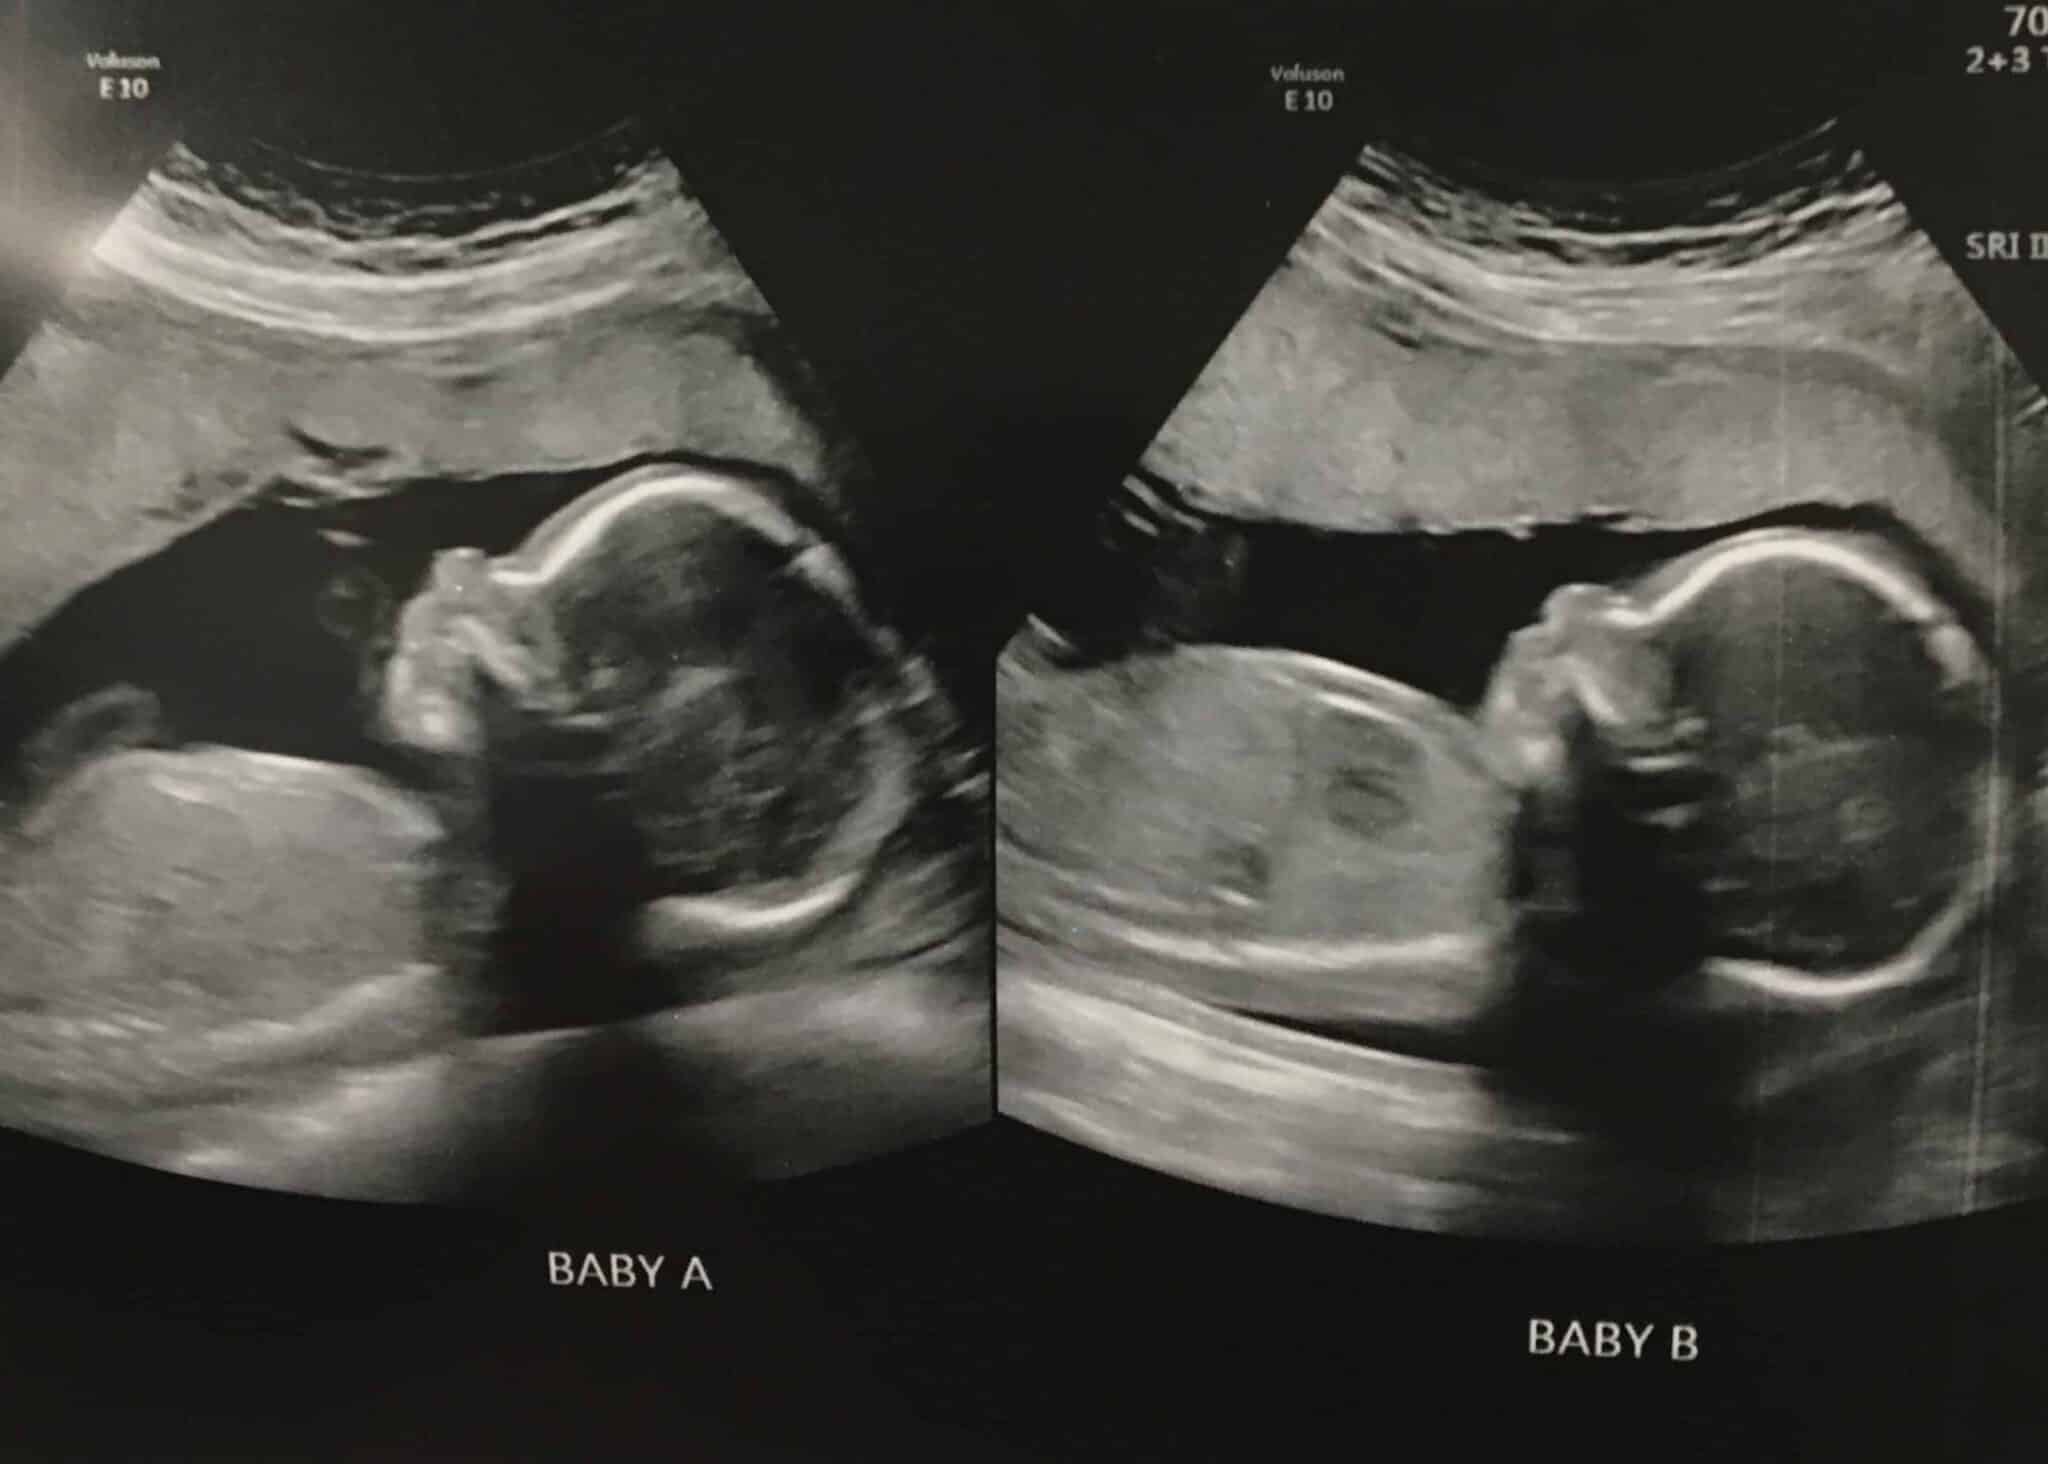

Ultrasound Photos at 30 Weeks Pregnant With Twins